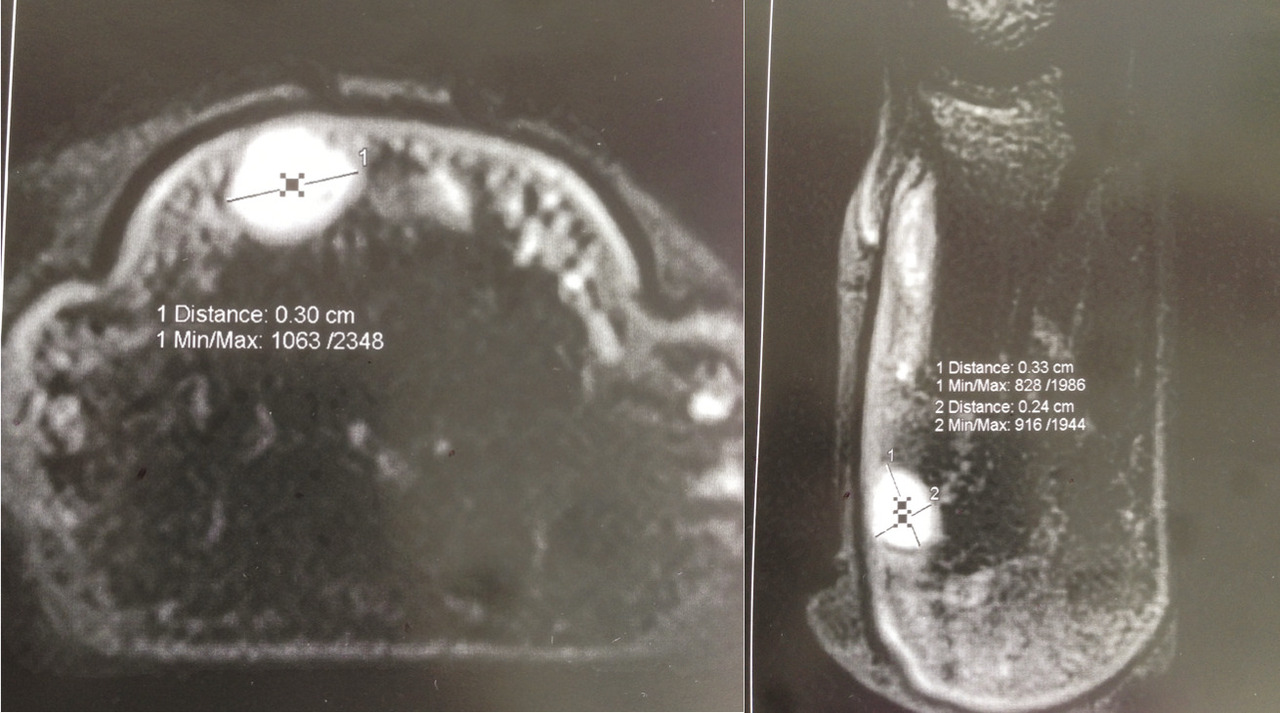

L’imagerie par résonance magnétique (IRM) avec utilisation d’antennes de surface adaptées aux doigts est l’examen de choix. Elle montre un signal T1 hypo-intense et un signal T2 hyperintense avec rehaussement sur les images pondérées en T1 après injection de gadolinium (fig. 3).21